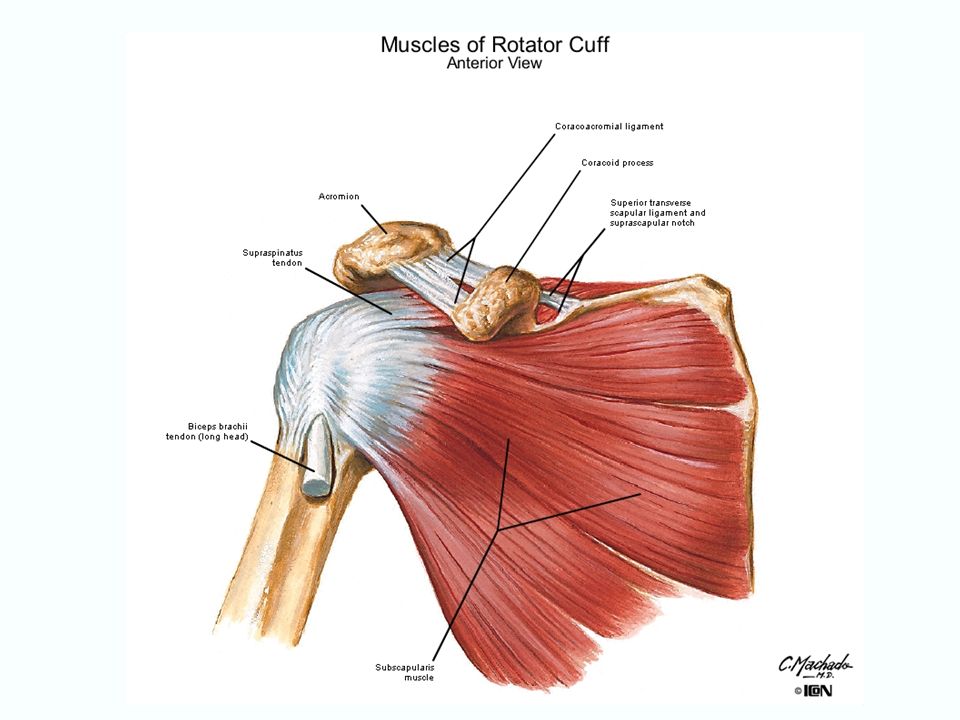

Фотографии мышц ротаторной манжеты плеча